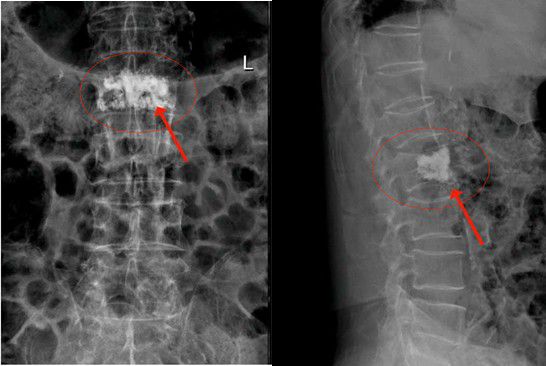

經内科綜合治療後,2月14日陳大伯身體各項指征平穩,可耐受手術。吳主任根據術前方案,爲老人家實施椎體成形術。在我院先進的術中三維CT機引導下,準确将2根穿刺針經雙側椎弓根穿入骨折椎體内,通過穿刺針建立通道注入骨水泥。術中三維CT機監視骨水泥分布良好,順利完成手術。手術切口小,無須縫合。由于采用局麻,術中陳大伯甚至還可以和醫護人員對話。注入的骨水泥支撐起原本空洞的椎體,骨水泥凝固後使病變的椎體迅速恢複了承重能力。

經内科綜合治療後,2月14日陳大伯身體各項指征平穩,可耐受手術。吳主任根據術前方案,爲老人家實施椎體成形術。在我院先進的術中三維CT機引導下,準确将2根穿刺針經雙側椎弓根穿入骨折椎體内,通過穿刺針建立通道注入骨水泥。術中三維CT機監視骨水泥分布良好,順利完成手術。手術切口小,無須縫合。由于采用局麻,術中陳大伯甚至還可以和醫護人員對話。注入的骨水泥支撐起原本空洞的椎體,骨水泥凝固後使病變的椎體迅速恢複了承重能力。

△術後,病變的椎體迅速恢複了功能